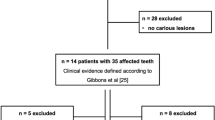

The overall extent of the bone edema of the endodontically treated teeth measured on MRI was also significantly larger compared to the radiolucencies measured on OPT and periapical radiographs (rater 1 mean STIR 2.2 ± 0.6 mm, dental radiograph 1.1 ± 0.5 mm, OPT 0.9 ± 0.9 mm, P = 0.04; rater 2 mean STIR 2.3 ± 0.9 mm, dental radiograph 1.2 ± 0.3 mm, OPT 0.7 ± 2.3 mm, P = 0.03), which was similar for the non-treated teeth (rater 1 STIR 2.6 ± 1.2 mm, dental radiograph 1.2 ± 0.7 mm, OPT 1.1 ± 0.9 mm, P = 0.01; rater 2 STIR 2.2 ± 0.9 mm, dental radiograph 1.0 ± 0.8 mm, OPT 0.9 ± 1.1 mm, P = 0.01) (Fig. 3).

a OPT of a 66-year-old patient with a carious lesion and periodontal disease of the tooth 36. Note the small periapical lesion on the conventional OPT (white arrow). On the sagittal reconstruction of the 3D STIR sequence (b), an extensive alveolar bone marrow edema (arrows) is detected which might indicate a markedly larger extent of the inflammation. Compared to MRI, the extent of inflammatory reaction may be underestimated by conventional OPT